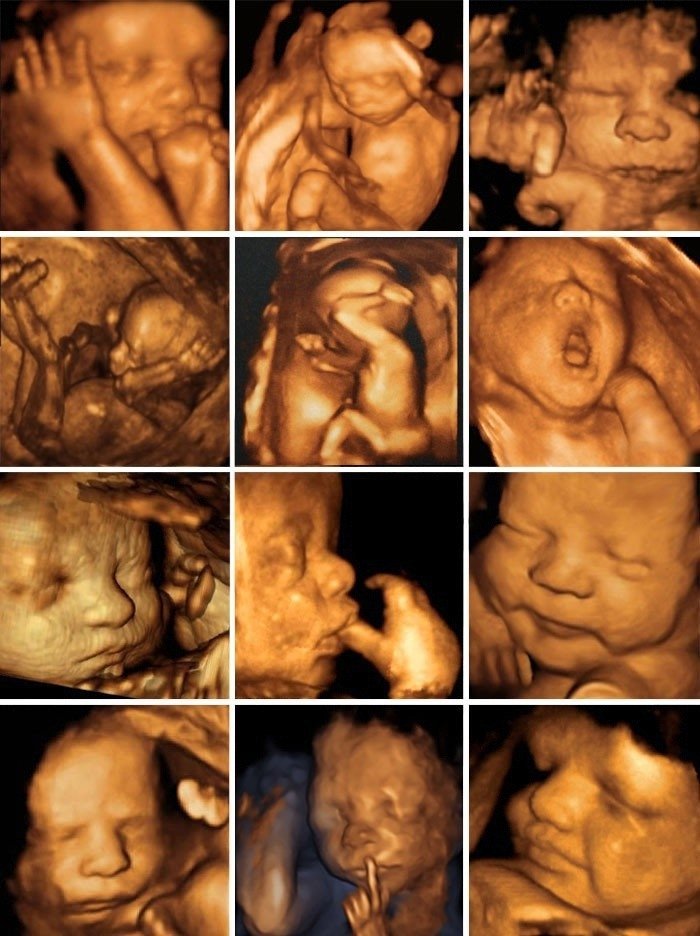

При трёхмерном УЗИ изображение получается объёмное, трёхмерное, но статичное. Теперь мы уже можем познакомиться с малышом: увидеть его черты лица, мимику и даже как он зевает или улыбается.

Первая фотография малыша — это изображение, получаемое при 3Д УЗИ

Когда есть возможность записать ультразвуковое исследование в режиме реального времени, то есть картинка уже получается не статичная, а движущаяся, тогда это уже четырёхмерное исследование. При таком УЗИ будущие родители могут пополнить свою видеотеку небольшим роликом с малышом в главной роли.